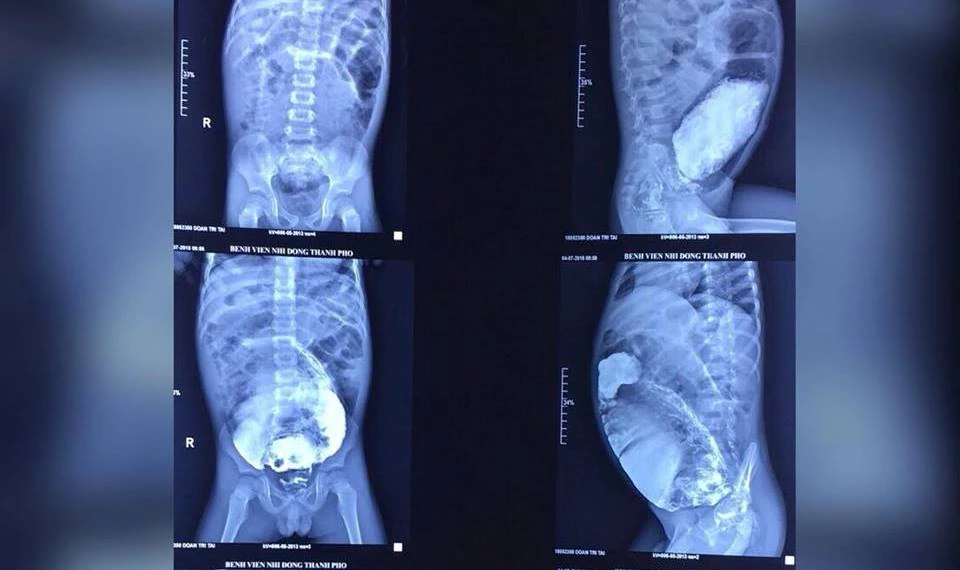

Hình ảnh đại tràng dãn to, ứ đầy phân của bé trai. Ảnh: BV

Tại đây, các bác sĩ chẩn đoán bé bị hội chứng phình đại tràng bẩm sinh khiến một đoạn đại tràng không có dây thần kinh để kiểm soát sự co bóp đại tràng. Bác sĩ đã tiến hành cắt bỏ phần trực tràng bị phình dài gần 20 cm, dãn to 20 cm, cùng gần 3kg phân ứ đọng bên trong.